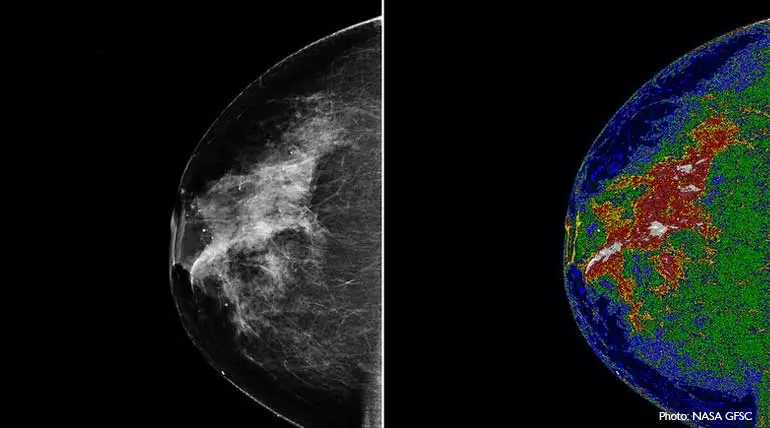

Tomosynthesis for women: With breast cancer for women on the rise, technology is lending a hand for its earlier deduction. One such new technology for testing breast cancer is Tomosynthesis or Tomo. It is a digital mammogram similar to the existing 2D digital mammography. But Tomo's advanced technology will capture images of the breast from multiple angles, unlike the 2D, which takes only two x-ray images, one from top to bottom and another from side to side angle.

Also, conventional 2D is limited by overlapping breast tissues. But with Tomo the x-ay tube moves in an arc over the compressed breast tissues to capture multiple images from different angles. Since it ensures a complete and accurate scan, it can even identify cancer cells in thick breast tissues of women.

Then the images are reconstructed into a set of 3D images in a computer system. The radiologist by examining the breast at multiple layers in depth will be better able to distinguish normal and tumor potential breast tissues. Doctors confirm that it will detect breast cancer in earlier stages for providing better chances of beating cancer.